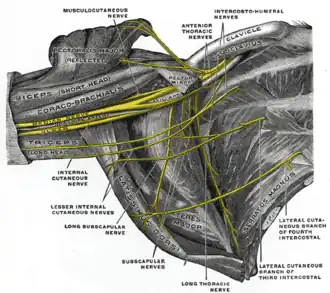

The right brachial plexus (infraclavicular portion) in the axillary fossa; viewed from below and in front.

The right brachial plexus (infraclavicular portion) in the axillary fossa; viewed from below and in front. -